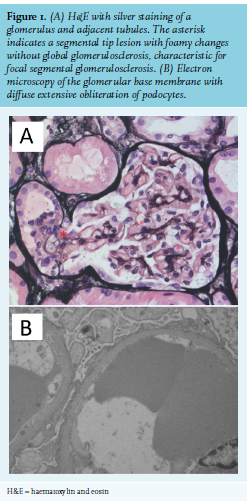

One year after cessation of the triamcinolone acetonide treatment in 2017, thrombocytopenia was progressive (33 x 109/l) and she developed a nephrotic syndrome with diffuse oedema and a 14 kg weight gain, hypoalbuminemia (albumin 22 g/l), heavy proteinuria (total protein 8.6 g/10 mmol creatinine), and an increase in creatinine from 81 to 105 µmol/l within two weeks. Serum complement levels were normal (C3 1.16 g/l, C4 0.35 g/l) and anti-phospholipase-A2-receptor (anti-Pla2R) was negative. Renal biopsy revealed a tip lesion variant of FSGS with negative immunofluorescence (IgA, IgG, IgM, kappa, lambda, C1q, C3, and Congo red) and no evidence of thrombotic microangiopathy (figure 1). The patient was treated with furosemide, angiotensin-converting enzyme inhibitor perindopril, and prednisolone (1 mg/kg). Within two weeks, the patient lost 12 kg, albumin levels increased to 24 g/l, protein excretion decreased to 1.7 g/10 mmol creatinine, and creatinine normalised. During the tapering of prednisone to 40 mg, protein excretion increased to 2.7 g/10 mmol creatinine. Because of side effects of long-term corticosteroid usage, rituximab was given as a corticoid-sparing agent. Five months later, kidney function normalised (creatinine 62 µmol/l; albumin 37 g/l; urinary total protein 0.09 g/10 mmol creatinine).